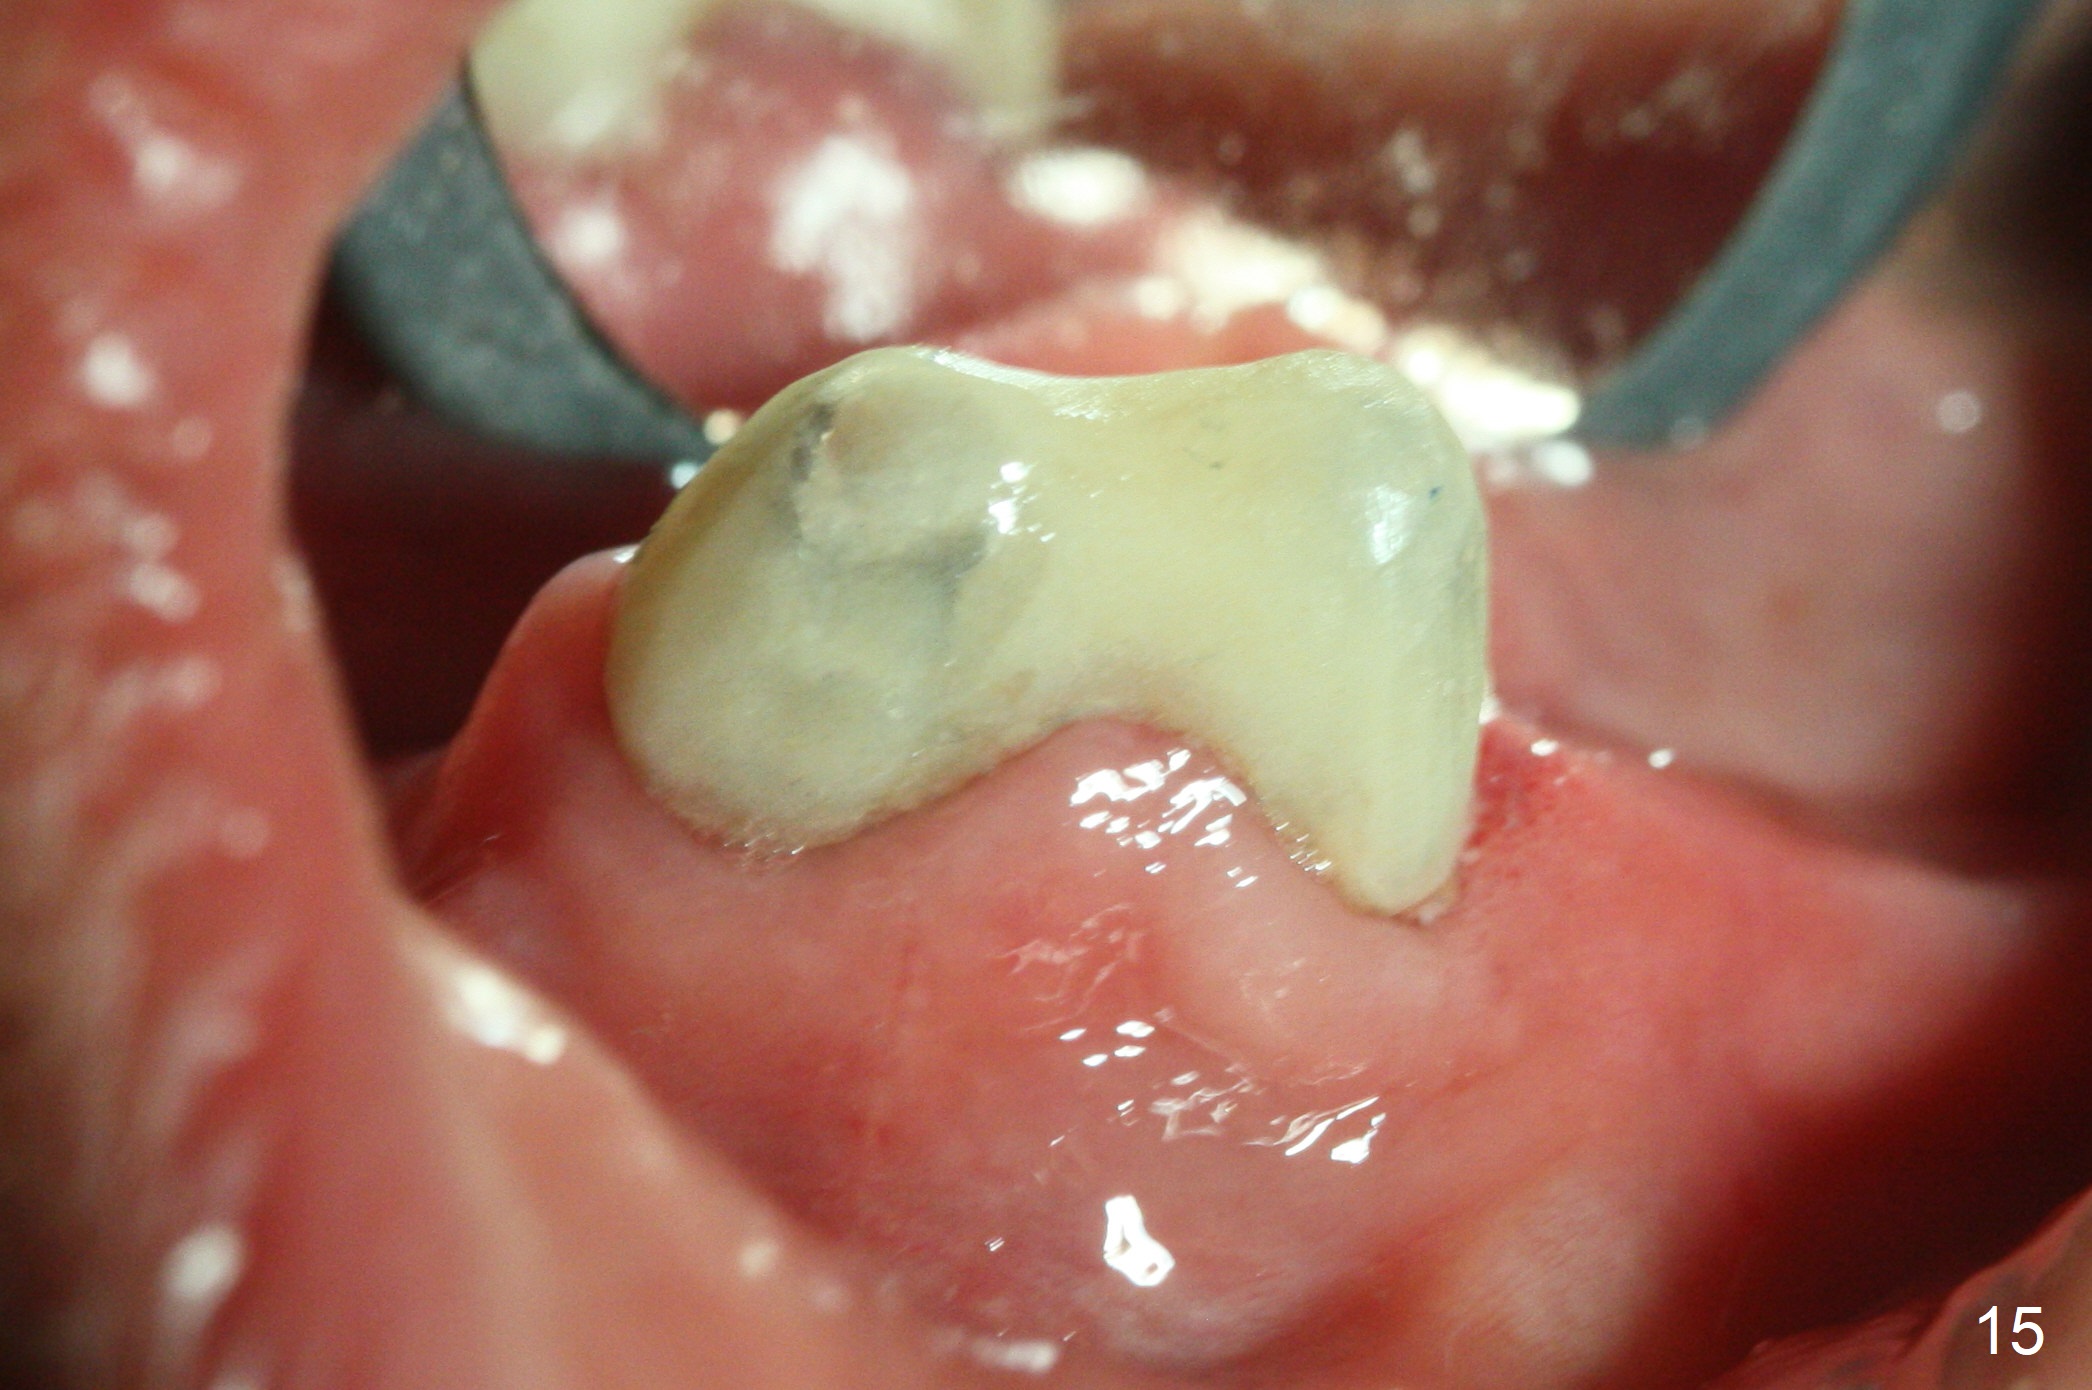

After change in abutment at #27 and abutment height adjustment at #26 and 27 (Fig.13), splinted provisional is fabricated with clearance from the RPD (Fig.14) and seal of the sockets (Fig.15). Acute submandibular and submental cellulitis develops with sublingual purulent discharge 1 month 10 days postop (Fig.16). CT confirms lingual plate perforation at both sites (Fig.17,18; red line: original socket). With block anesthesia, removal of these implants causes mild discomfort. With Hydrogen Peroxide and normal saline copious irrigation, pain reduces when anesthesia subsides. Bone graft will be placed at the sites approximately in 2 weeks. In fact the infection is not controlled until 2 weeks later (Fig.19). The clasp has to be covered with acrylic for comfort (Fig.20). The previous implant sites heal 1.5 months post implant removal (Fig.22).